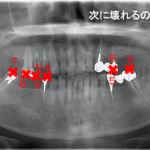

フルマウス(全顎)治療とは

虫歯や歯周病、噛み合わせ、インプラント、矯正、審美治療などあらゆる分野から総合的に歯の治療を行い、機能性と見た目の両方に配慮した治療のことです。